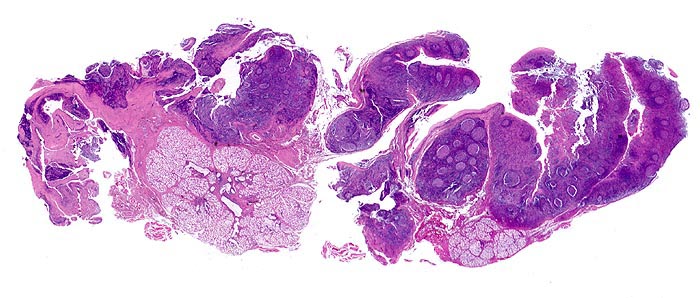

Lymphknoten, lymphatisches Gewebe des Oropharynx und Tonsillen zeigen ähnliche Veränderungen:

• Aktivierung der B-Lymphozyten-Areale (EBV induzierte polyklonale Infektion und Stimulation der EBV-Rezeptor tragenden B-Zellen): grosse, aktivierte Keimzentren (=follikuläre Hyperplasie), aktive parafollikuläre Plasmazellbildung (B-Immunoblasten, Plasmoblasten, Plasmazellen).

• Aktivierung der interfollikulären T-Zone (= sogenannte bunte Pulpahyperplasie) mit Hodgkin-artigen Zellen (= reaktive/aktivierte B- resp. T-Lymphozyten).

• Von nicht verhornendem Plattenepithel bedeckte Gaumentonsille.

• Follikuläre Hyperplasie:

Reaktive Keimzentren mit Zentrozyten, grösseren Zentroblasten und Kerntrümmermakrophagen. Follikel mit dunkler Mantelzone.

• Interfollikuläre Hyperplasie der T-Zone (bunte Pulpahyperplasie):

Hodgkinartige Zellen (=reaktive/aktivierte B- resp. T-Lymphozyten), kleine Lymphozyten, Immunoblasten mit zentralem Nukleolus und Plasmazellen.

• Hochendotheliale postkapilläre Venolen (gesteigerte Lymphozyten-Rezirkulation).